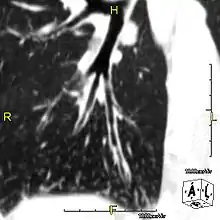

Around 80% of people with primary ciliary dyskinesia experience respiratory problems beginning within a day of birth. Many have a collapsed lobe of the lung and blood oxygen low enough to require treatment with supplemental oxygen.[3] Within the first few months of life, most develop a chronic mucus-producing cough and runny nose.[3] The main consequence of impaired ciliary function is reduced or absent mucus clearance from the lungs, and susceptibility to chronic recurrent respiratory infections, including sinusitis, bronchitis, pneumonia, and otitis media. Progressive damage to the respiratory system is common, including progressive bronchiectasis beginning in early childhood, and sinus disease (sometimes becoming severe in adults). However, diagnosis is often missed early in life despite the characteristic signs and symptoms.[4] In males, immotility of sperm can lead to infertility, although conception remains possible through the use of in vitro fertilization, there also are reported cases where sperm were able to move.[5] Trials have also shown that there is a marked reduction in fertility in females with Kartagener's syndrome due to dysfunction of the oviductal cilia.[6]

Many affected individuals experience hearing loss and show symptoms of otitis media which demonstrates variable responsiveness to the insertion of myringotomy tubes or grommets. Some patients have a poor sense of smell, which is believed to accompany high mucus production in the sinuses (although others report normal – or even acute – sensitivity to smell and taste). Clinical progression of the disease is variable, with lung transplantation required in severe cases. Susceptibility to infections can be drastically reduced by an early diagnosis. Treatment with various chest physiotherapy techniques has been observed to reduce the incidence of lung infection and to slow the progression of bronchiectasis dramatically. Aggressive treatment of sinus disease beginning at an early age is believed to slow long-term sinus damage (although this has not yet been adequately documented). Aggressive measures to enhance clearance of mucus, prevent respiratory infections, and treat bacterial superinfections have been observed to slow lung-disease progression. The predicted incidence is 1 in approximately 7500.[7]

Several diagnostic tests for this condition have been proposed.[16] These include nasal nitric oxide levels as a screening test, light microscopy of biopsies for ciliary beat pattern and frequency and electron microscopic examination of dynein arms, as the definite diagnosis method. Genetic testing has also been proposed but this is difficult given that there are multiple genes involved.